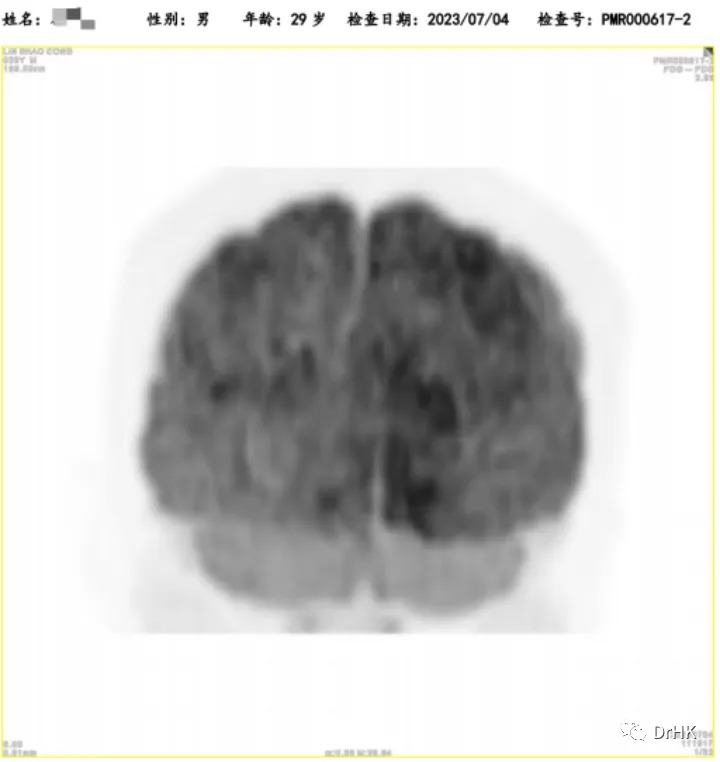

Starting from April 2, 2022, the patient was treated with the DA-TEDDi-R regimen combined with targeted therapy (ibrutinib + rituximab + dexamethasone + liposomal doxorubicin + etoposide + temozolomide + long-acting GCS + intrathecal Ara-C) for two cycles. After the treatment, the PET-CT assessment showed complete metabolic remission (the first complete remission since the onset of the disease), with a Deauville score of 2-3. Comparing this with the PET/CT imaging from our center on April 1, 2022, the liver lesion significantly decreased and the high metabolic activity disappeared; the left gluteus maximus lesion also disappeared. There were localized bone resorption and destructive changes in multiple bones (bilateral scapulae, clavicles, ribs, sternum, pelvic bones, and vertebrae), with some areas showing increased bone density, particularly in the left iliac bone. The bone marrow glucose metabolism was diffusely elevated, suggesting reactive changes post-treatment, and we recommended further evaluation with a bone marrow biopsy.

After achieving the first treatment goal, we proceeded with the second autologous transplantation combined with CAR-T cell therapy as a consolidation treatment. This time, we used the TEAM regimen for conditioning (tirofiban + etoposide + cytarabine + mafosfamide) and prepared and infused CD19/CD20 dual-target CAR-T cells. The treatment process was relatively smooth. After the CAR-T cell infusion, the patient started experiencing fever on day 5, with a peak temperature of 39°C on day 8. This was diagnosed as cytokine release syndrome (CRS), classified as grade I, with no signs of immune effector cell-associated neurotoxicity syndrome (ICANS). CAR-T cell expansion was detected, and the patient's granulocytes engrafted on day 14 (July 5, 2022) after autologous hematopoietic stem cell infusion, and platelets engrafted on day 12 (July 3, 2022) after the same infusion. After the transplant, the patient was given oral ibrutinib as maintenance therapy.

5. Follow-up

The patient was subsequently followed up regularly, with imaging evaluations completed six months and one year after the transplant. It is gratifying to report that the patient has maintained complete remission throughout this period. The PET images are shown below:

Six-Month Post-Transplant Imaging Evaluation

One-Year Post-Transplant Imaging Evaluation